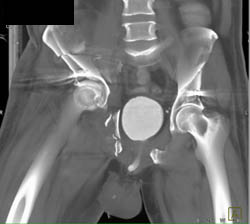

Normal Vessel Trifurcation S/P Soft Tissue and Muscle Trauma